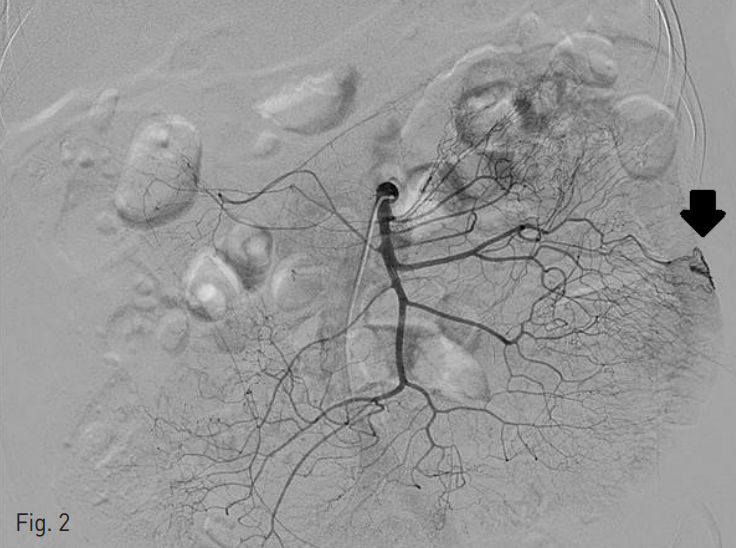

오른쪽 대퇴동맥을 통해 5 Fr 카테터 (RH, Cook, Bloomington, IN)를 삽입하여 상장간동맥 조영술을 시행하였다. 상장간동맥의 공장 가지에 약 1cm 크기의 구불구불한 모양의 늘어난 혈관이 있으면서 조기 배액되는 정맥 병변을 동반하여 혈관형성이상 병변으로 생각하였다 (Fig. 2). 이에 대해 2.0 Fr 미세카테터(Progreat, Terumo, Tokyo, Japan)를 이용하여 공장가지에 접근 하였고, 0.5cc 용량의 glue (Histoacryl, B.Braun, Tuttlingen, Germany) 1 vial을 Lipiodol (리피오돌울트라액, Guerbet, France)과 함께 1:3의 비율로 혼합하여 색전술을 시행하였다 (Fig. 3). 이후 시행한 동맥조영술에서 남아있는 병변이 없는 것을 확인하고 시술을 종료하였다.

Fig. 2

There is an angiodysplasia in the jejunal branch of superior mesentery artery.